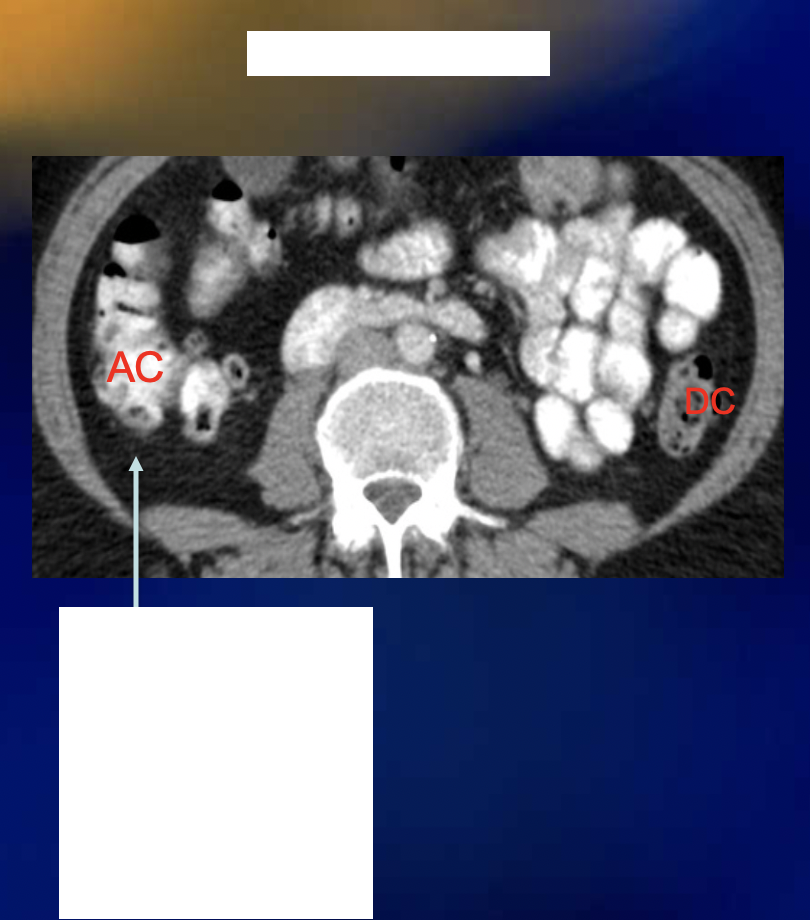

Is this normal fat or abnormal fat?

What is seen on the ascending colon?